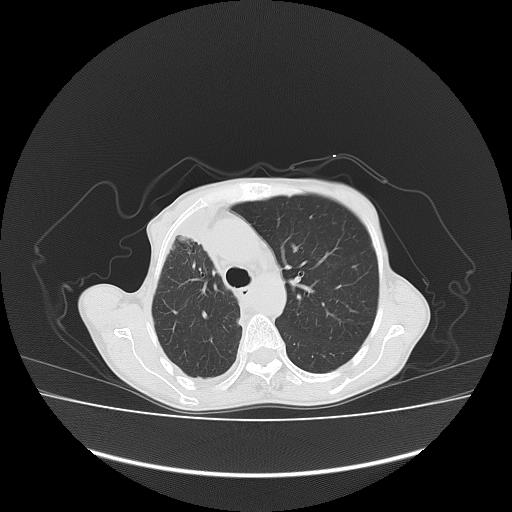

标题: CT16930:女 59 胸痛6个月 胸水脱落细胞学见瘤细胞 [打印本页]

标题: CT16930:女 59 胸痛6个月 胸水脱落细胞学见瘤细胞

可见多发肺内病灶,且胸膜病灶较多有圆球状而非丘状,多考虑胸膜转移瘤伴胸腔积液,右侧胸廓缩小固定,且部分病灶呈丘状,尚不除外恶性胸膜间皮瘤伴肺内转移

右侧胸膜增厚,局部呈结节状增厚,右侧胸腔少量积液。双肺未见确切肿块影。纵隔未见淋巴结肿大。气管、支气管通畅。考虑右侧胸膜间皮瘤(恶性?)可能性大。不除外癌性胸膜炎。

恶性胸膜间皮瘤伴肺内转移可能性大;或胸膜、肺内均为转移瘤,左肺下叶亦见多发小结节影。

右侧胸廓塌陷,右侧胸膜广泛增厚并见多发胸膜结节,右侧少量胸腔积液并包裹。

右侧广泛胸膜增厚,局部呈结节状增厚,右侧胸腔少量积液。双肺未见确切肿块影。纵隔未见淋巴结肿大。气管、支气管通畅。考虑右侧胸膜间皮瘤(恶性?)可能性大。支持!

右侧胸膜转移瘤,原发灶可能就在在右肺,另外建议检查右侧乳腺.

右胸腔结节均考虑来自胸膜(部分来源于叶裂),考虑胸膜间皮瘤或转移瘤.